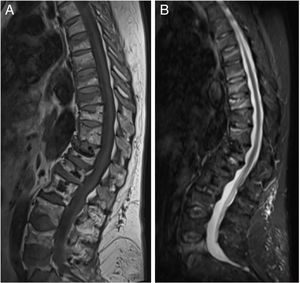

ResultsThe characteristics of the patients are shown in Table 1. Their average age at the start of treatment was 66 ± 7.7 years. Four patients had a previous history of fractures due to fragility, and only one had risk factors for secondary OP (aromatase inhibitors, case 7). Nine patients (90%) had received other treatments prior to commencing with DMab (7 oral bisphosphonates, 5 strontium ranelate, 2 raloxifene, 1 tibolone and 1 calcitonine). The patients received from 3 to 9 doses of DMab, following the dosage recommended in its technical data sheet, with an average of 6 ± 1.7. The reason for withdrawal of the drug was dental work (cases 1 and 6), low risk of fracture (case 5) and termination of the time set by the prescribing doctor. In all cases except two bone density had been measured before starting with DMab. The average T-score before treatment was -2.6 ± 0.6 in the femoral neck (FN) and -3.0 ± 1.3 in the lumbar spine (LS). Likewise, in all of the cases except two (cases 7 and 9) densitometry was performed at least 6 months after the withdrawal of the treatment, with an average T-score of -3.2 ± 0.7 in the FN and -3.2 ± 1.6 in the LS. The bone turnover markers at least 10 months after discontinuation were found to be high, with a collagen telopeptide average (CTX) of 1.32 ± 0.32 ng/ml, and collagen propeptide (P1NP) of 181.6 ± 104.1 ng/ml. The time between the last dose of the drug and the appearance of the first fracture varied from 8 to 18 months, with an average of 10.9 ± 3.3 months. The patients suffered from 2 to 9 fractures, and a total of 49 fractures were recorded. Fig. 1 shows the diagnostic imaging tests corresponding to case 10. In all cases the fractures occurred spontaneously, without associated trauma. The vertebras affected the most often were L3, L5, D6, D7, D9 and D11. Two patients (cases 1 and 2) received vertebroplasty, and new vertebral fractures occurred in both patients. One patient (case 9) commenced taking alendronate six months after discontinuing DMab, following the recommendations of the European Calcified Tissue Society (ECTS), and in spite of this suffered vertebral fractures (Fig. 2). Respecting the pharmacological treatment received after the fractures, the options used the most often were teriparatide (30%), oral bisphosphonates (20%) and DMab (20%).